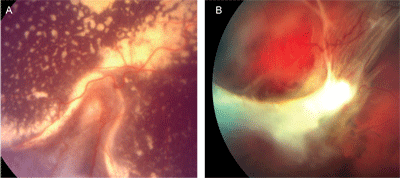

Logar J, Soba B, Kraut A, Stirn-Kranjc B đang công tác tại khoa ký sinh trùng, Viện vi trùng và miễn dịch, khoa y, đại học Ljubljana, Slovenia vừa đăng trên tạp chí Korean J Parasitol. 2004 Sep;42(3):137-40 bài viết này. Bệnh ấu trùng giun đũa chó mèo ở mắt còn gọi là Ocular toxocariasis gây ra bởi ấu trùng giun tròn Toxocara spp. Mục đích của nghiên cứu này là tìm ra tỷ lệ huyết thanh dương tính của các kháng thể của Toxocara trên các bệnh nhân nghi ngờ bị OLM.

Từ năm 2001-2003, huyết thanh của 239 bệnh nhân có vấn đề về mắt, tuổi từ 3-80 được kiểm tra bằng ELISA và xác định lại bằng Western blot test. Trong số 239 bệnh nhân, có 172 (72%) âm tính và67 (28%) là huyết thanh dương tính Toxocara; 95% CI (22-34%). Tuổi trung bình của bệnh nhân nhiễm dương tính huyết thanh là 37.6 tuổi. Không có sư khác biệt có ý nghĩa thống kê trong số huyết thanh dương tính Toxocara trong số các nhóm tuổi nhỏ (< hoặc = 14 tuổi) và nhóm tuổi lớn hơn (> 14 tuổi), p > 0.05. Một tỷ lệ cao về tỷ lệ huyết thanh dương tính trên các bệnh nhân về mắt nên đưa ra cảnh báo với các nhà nhãn khoa tại Slovenia để đưa bệnh ấu trùng giun đũa chó này vào chẩn đoán phân biệt với các bệnh mắt thường gặp.